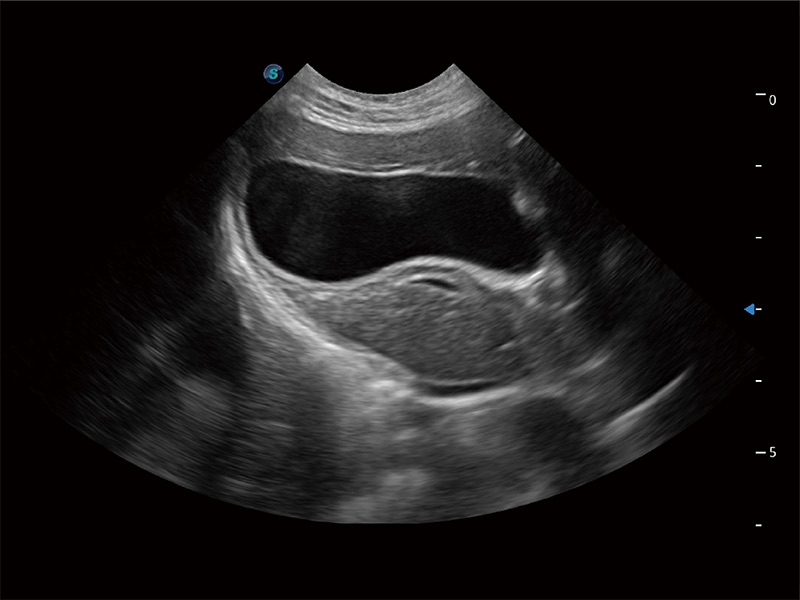

动物是人类最亲密的朋友和最值得信赖的伙伴。MILE米乐集团官网也一直致力于探索动物专用的超声影像解决方案。全新推出的ProPet系列,是MILE米乐集团官网在动物超声影像智能化、专业化、精准化的一次跨越式革新。动物不能用言语来表述自己的不适,通过超声影像,ProPet系列搭建了动物医生与不同物种沟通的“桥梁”,为动物医生注入了“治愈之力”。 ProPet 80 是MILE米乐集团官网匠心打造的一款高端动物专用彩超,采用性能卓越的全新硬件架构,极大提升超声系统的运行效率和数据处理能力,帮助动物医生从容应对日益增多的挑战性病例和日益多样化的临床需求。

高性能和先进的临床应用工具可以为动物医生提供临床信心。ProPet 80 搭载了先进的腹部和浅表应用工具,帮助医生在日常临床实践中发挥前所未有的作用。

一键自动识别膀胱壁及自动测量膀胱容积,不受膀胱形状和大小的限制,帮助医生快速精准获得测量的数据。